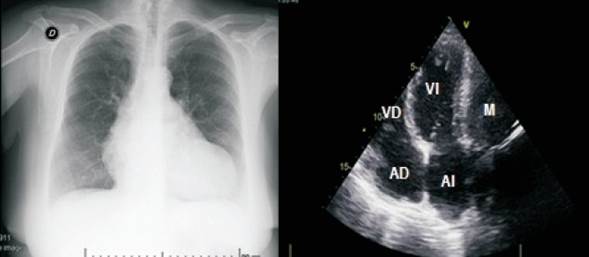

Se realiza radiografía de tórax de frente (figura 2), que muestra un índice cardiotorácico conservado, sin signos de hipertensión venocapilar pulmonar. Superpuesto a la imagen cardíaca en tercio inferior del hemitórax izquierdo, se observa imagen redondeada, bien delimitada, de 8 cm de diámetro mayor, con densidad homogénea similar a la de la silueta cardíaca.

Figura 2: A la izquierda, radiografía de tórax frente en el que se muestra imagen redondeada, delimitada de unos 8 cm de diámetro con densidad similar a la cardíaca. A la derecha, ecocardiograma transtorácico en ventana apical de cuatro cámaras que visualiza masa extracardíaca en relación con pared lateral del ventrículo izquierdo. AD: aurícula derecha; AI: aurícula izquierda; VD: ventrículo derecho; VI: ventrículo izquierdo; M: masa paracardíaca.

El ecocardiograma transtorácico (figura 2) informa una fracción de eyección del ventrículo izquierdo normal y denota una compresión extrínseca de la pared libre del ventrículo izquierdo.